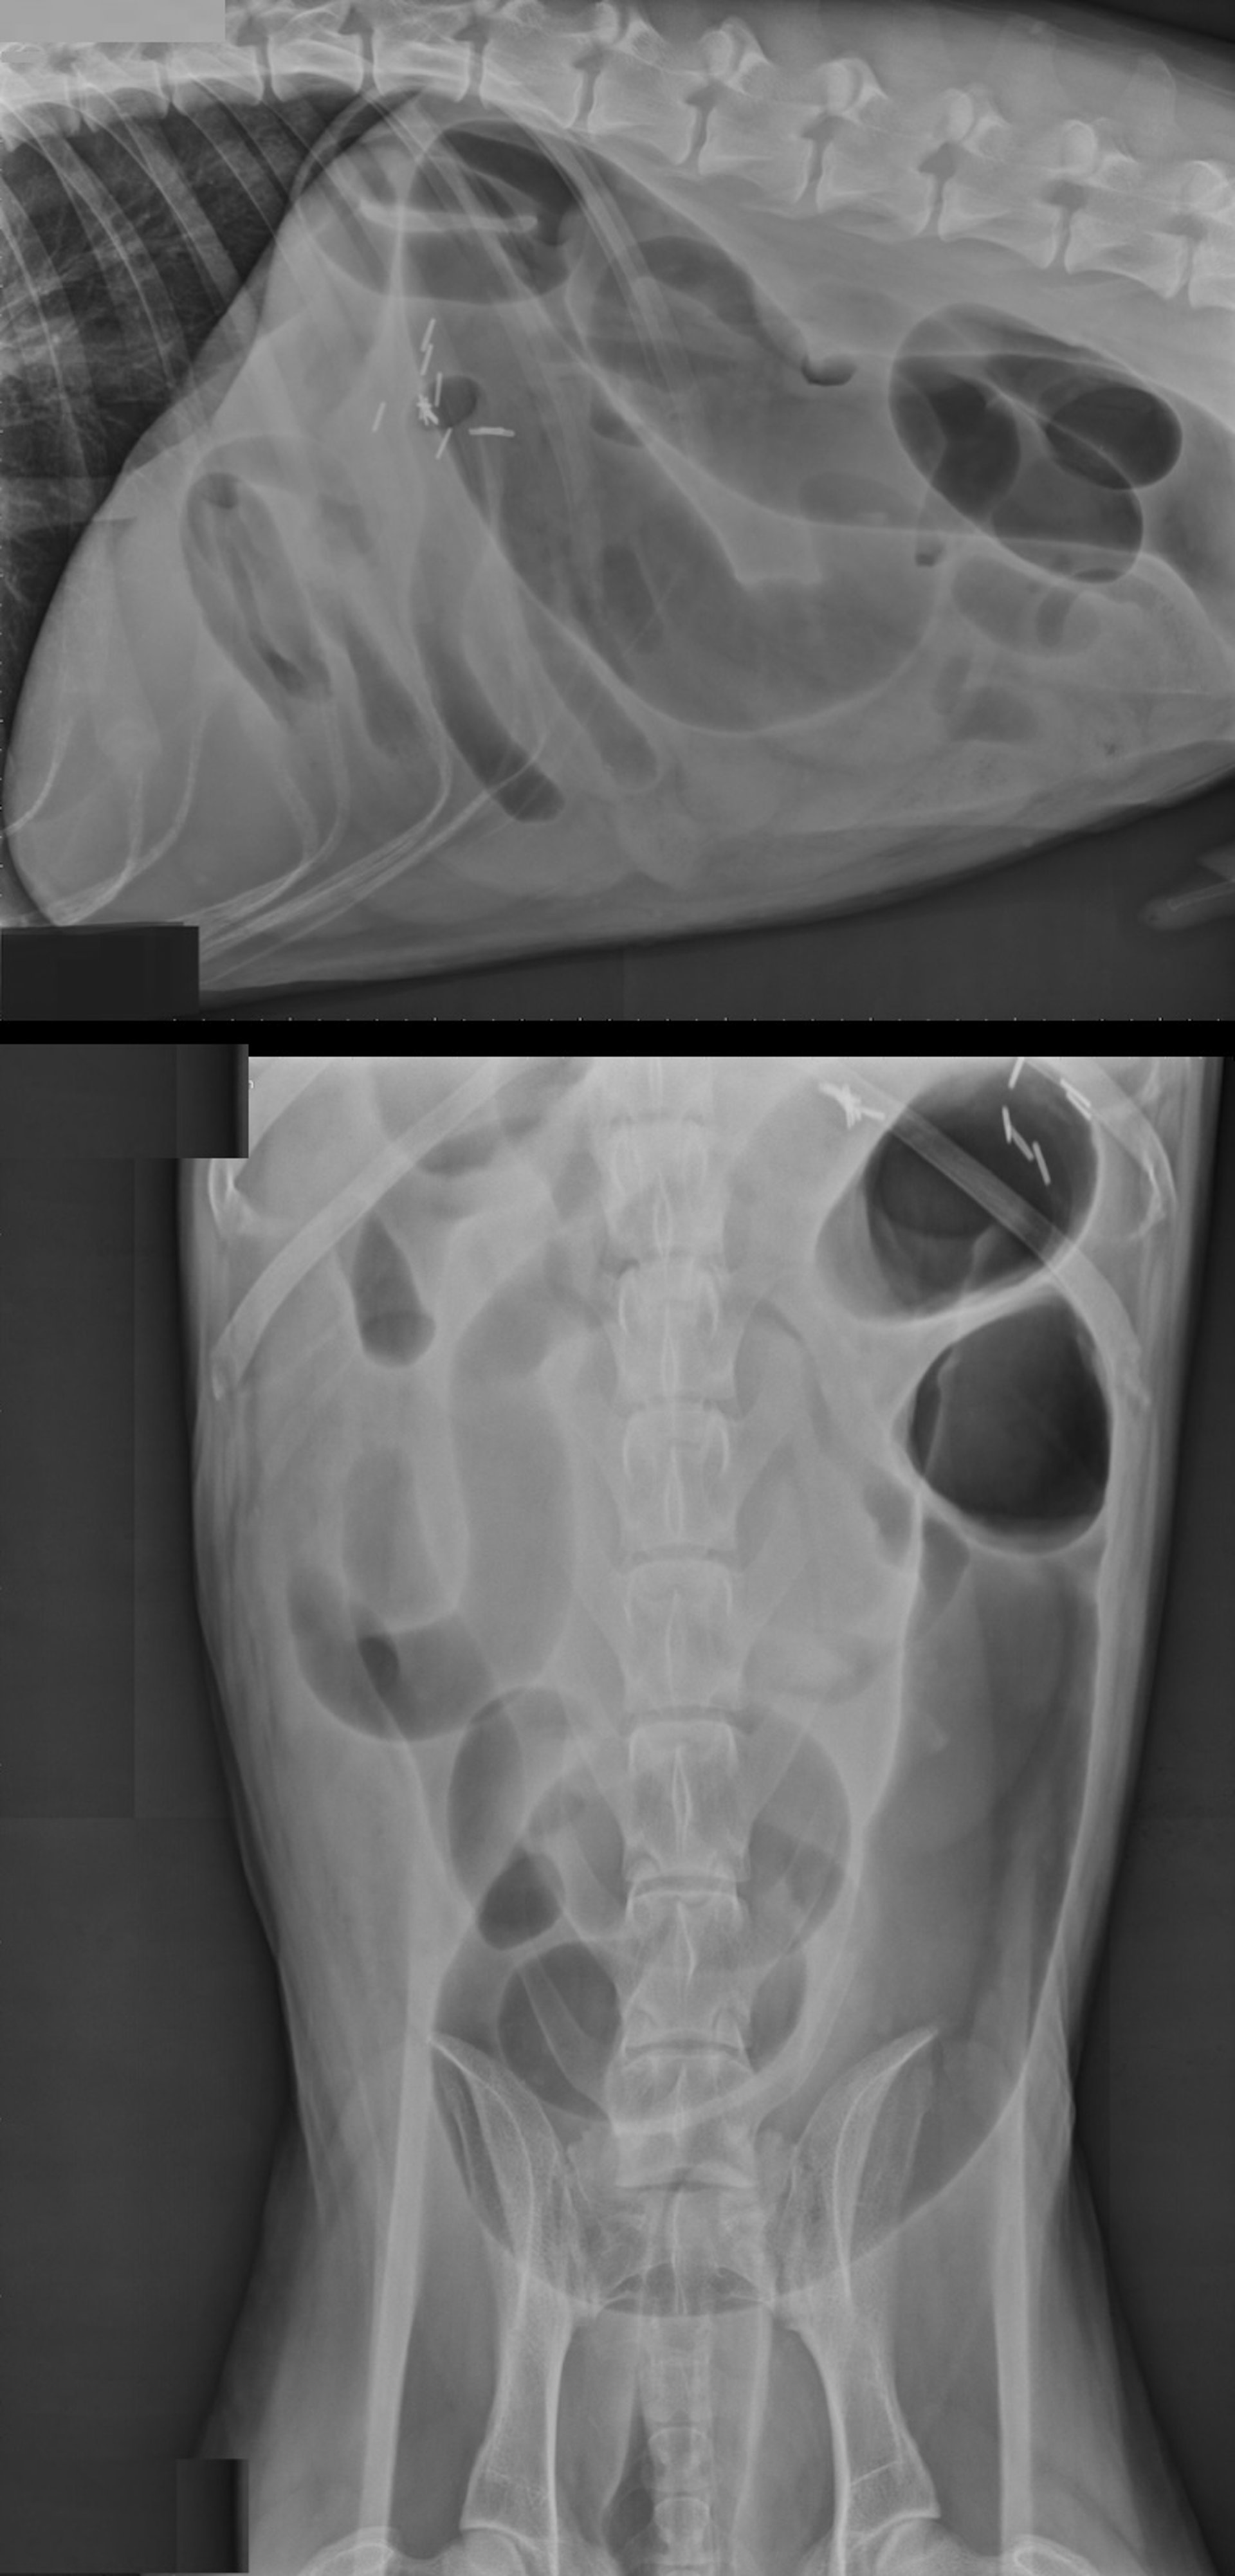

Intestinal volvulus, radiographs, lateral and ventrodorsal views, dog

Lateral and ventrodorsal radiographs of a 2-year-old neutered male German Shepherd Dog with intestinal volvulus (colonic torsion in addition to a partial torsion of the small intestine). On the lateral projection, note the large gas-filled colon that deviates downward at the level of the pelvis. Additionally, there are multiple gas-filled loops of small intestines. On the ventrodorsal projection, note the large gas-filled colon in an abnormal position in the left side of the abdomen. The metal clips are residual from a previous gastric dilation and volvulus surgery 1 year earlier.

Courtesy of Dr. Kevin Winkler.